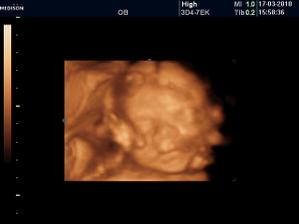

Vyrobene z velkej lasky

diky lutsine. no vobec nebolo vidno....ale uz mi je tazsie brusko ted to tak pocitujem ze ledva sa obujem.